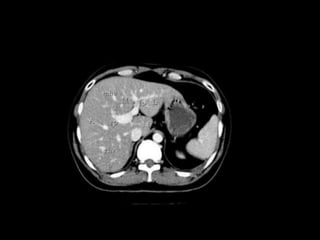

Anatomy of the liver segments

Right hepatic vein divides the right lobe into anterior and posterior

segments.

Middle hepatic vein divides the liver into right and left lobes (or right

and left hemiliver).This plane runs from the inferior vena cava to the

gallbladder fossa.

The Falciform ligament divides the left lobe into a medial- segment IV

and a lateral part - segment II and III.

The portal vein divides the liver into upper and lower segments.

The left and right portal veins branch superiorly and inferiorly to project

into the center of each segment.

Anatomy of liver segments

segment I : is the caudate lobe situated posteriorly around the IVC and different to

the other 7 segments. It may receive its supply from both the right and the left portal

vein and is drained directly into the IVC by one or more small hepatic veins

The remainder of the segments (II toVIII) are numbered in a clockwise fashion

starting superiorly in the left hemiliver :

segments II and III : are lateral to the left hepatic vein and falciform ligament with II

superior and III inferior to the portal plane

segment IV : lies medial to the falciform ligament, between the left and middle

hepatic veins. It is subdivided into IVa (superior) and IVb (inferior) subsegments. Easy

tip: IVa above and IVb below the portal plane. Segment IV includes the quadrate lobe.

SegmentV toVIII make up the right hemiliver and are easier to describe:

segmentV : is located below the portal plane between the middle and right hepatic

veins

segmentVI : is located below the portal plane lateral to the right hepatic vein

segmentVII : is located above the portal plane lateral to the right hepatic vein

segmentVIII : is located above the portal plane between the middle and right hepatic